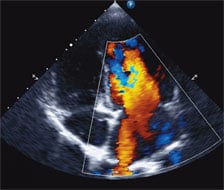

An echocardiogram showed evidence of severe right ventricular hypertension due to elevated pulmonary pressure, which was confirmed via catheterization. We diagnosed her with IPAH and immediately started her on pulmonary vasodilators in an effort to reduce the pulmonary pressures.

Done surgically, the Potts shunt carries a high morbidity and mortality rate. However, echocardiograms and a CT scan revealed a tiny patent ductus arteriosus (PDA) in our patient. While an incidental finding not related to her PH, it provided us with an opportunity to perform the shunt without surgery, something that had been done a few times in Europe.